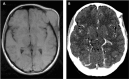

Background: Ewing sarcoma is a rare malignant neoplasm that is primarily localized in bone tissues. The prognosis for patients with a newly diagnosed localized Ewing sarcoma has been greatly improved by multimodality treatment. However, treating patients with disseminated or recurrent disease is challenging, with a 5-year overall survival rate of <30%. Case Report: A 17-year-old female with an asymptomatic tumor of the left temple underwent 3 cycles of vincristine, ifosfamide, doxorubicin, and etoposide and achieved partial remission. However, the patient refused further chemotherapy and surgical intervention and was lost to follow-up. After 7 months, the patient presented again with a sizeable tumor on her left temple and worsening symptoms. Chemotherapy with alternating cycles of vincristine, doxorubicin, cyclophosphamide, ifosfamide, and etoposide according to the EURO EWING 2012 trial was initiated. After a positive response, debulking surgery was performed, followed by postsurgical radiation, and partial remission was achieved. Conclusion: Optimal treatment protocols for recurrent Ewing sarcoma are lacking. Treatments are individualized based on the patient's response to treatment and the decisions of tumor boards. Patients with rare tumors such as Ewing sarcoma benefit from multidisciplinary collaboration, resulting in improved quality of care and treatment outcomes.